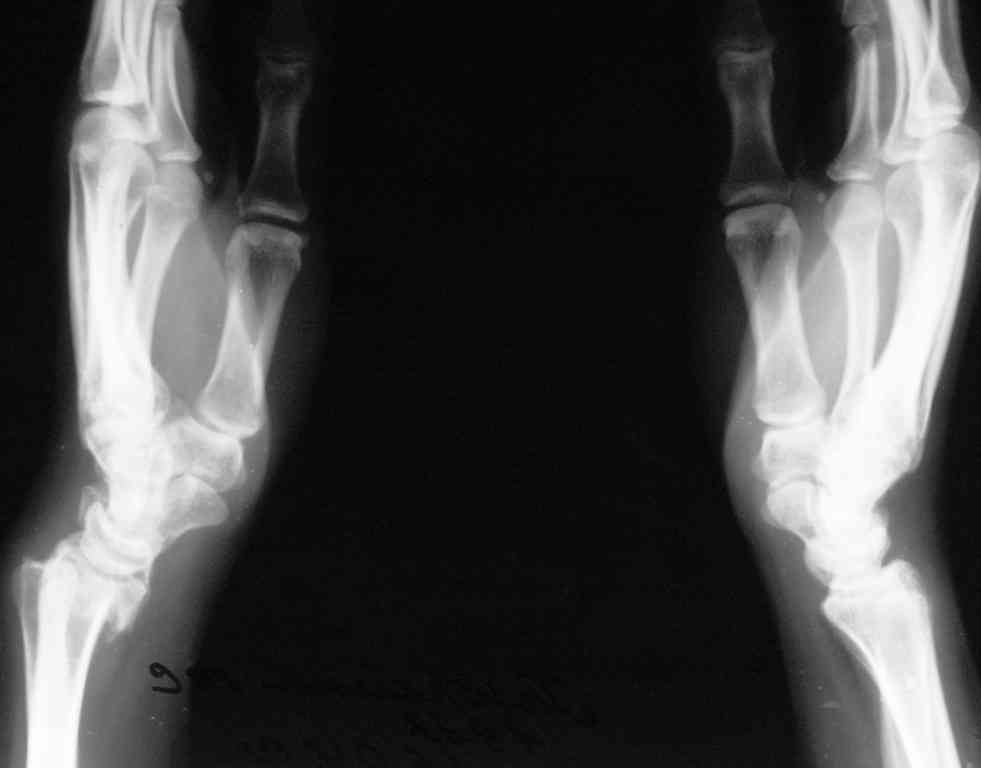

У больного/ой кроме перелома лучевой кости и шиловидного отростка локтевой, разрыв дистального радиоульнарного сочленения, перелом ладьевидной кости и ладьевидно-полулунная диссоциация.

Если позволите свое мнение, не стал бы лечить аппаратом эту травму, перелом луча не консолидировался: открытая репозиция+ костная пластика+ пластина, синтез ладьевидной кости, по возможности шов ладьевидно полулунной связки,

если восстановить связку не представляется возможным, фиксация 2 спицами.